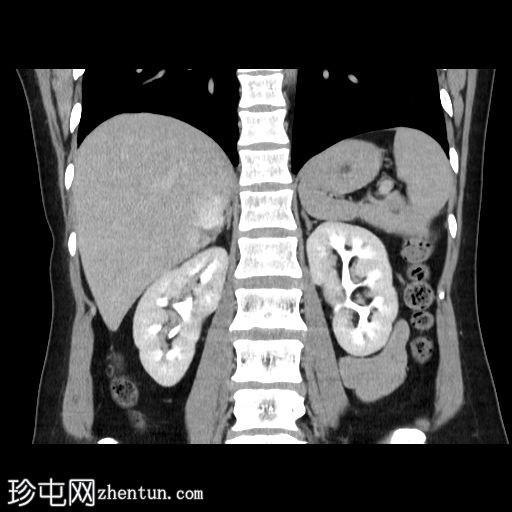

冠状面

非造影

在轴向、冠状面和矢状面上均可见肝5/6段病变。动脉期可见周围结节状强化,门静脉期可见进行性向心性充盈,延迟期亦持续存在。这些表现为肝血管瘤的特征性表现。